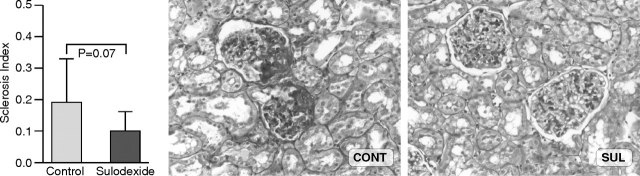

Glomerulosclerosis in sulodexide-treated rats trended to be less compared to controls (SI: 0.10 ± 0.06 vs 0.19 ± 0.10; SUL vs CONT, P = 0.07) (Figure 1). Mesangial expansion in CONT db/db mice was generally mild at sacrifice at 9 weeks, with an average of 87 ± 22% glomeruli with grade 2 mesangial expansion (range 78–94), vs 12 ± 6% with grade 3 lesions (range 24–22), similar to SUL db/db (grade 2, 84 ± 16%, range 48–96, grade 3, 16 ± 16%, range 4–52%, P = NS). Arteriolar hyaline was present in 12% of CONT and 16% of SUL.

Fig. 1.

Rats treated with sulodexide showed a trend for less glomerulosclerosis at 8 weeks compared to control animals (periodic acid-Schiff, ×200).

We found that sulodexide treatment could reduce the early manifestations of radiation nephropathy as shown by a significant reduction of proteinuria at 4 and 8 weeks and by a trend in reduction of serum creatinine at 8 weeks after radiation in treated animals compared to controls. There was a corresponding trend, albeit not statistically significant, for less glomerulosclerosis in animals receiving sulodexide compared to controls at 8 weeks. Neither albuminuria nor structural lesions in db/db mice were affected by sulodexide.